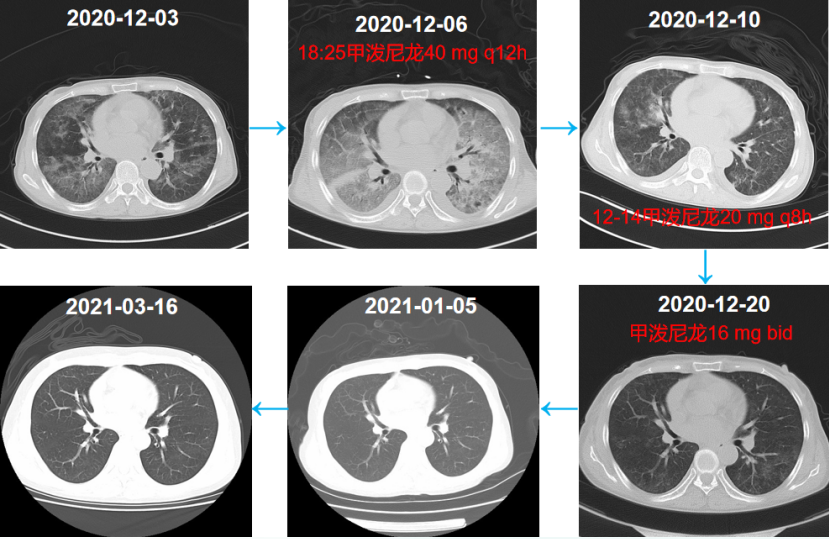

5  患者住院期间胸部CT变化情况

入院当天送KL-6快速进行性升高(图4)患者肺部后续出现机化和纤维化(图5)尽管整个治疗过程非常艰辛但最终预后比较满意。随访胸部CT可见病变吸收良好。